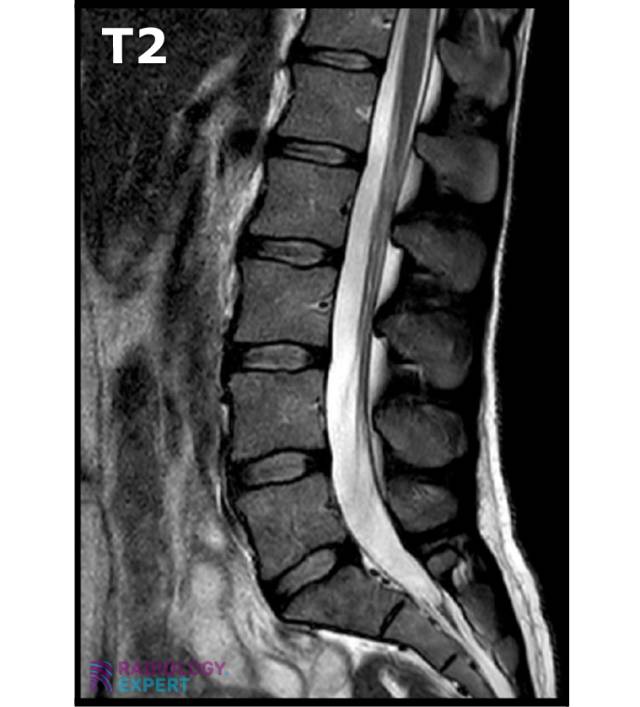

Anatomy MRI lumbar spine Anatomy MRI lumbar spine

Click image to see overlay